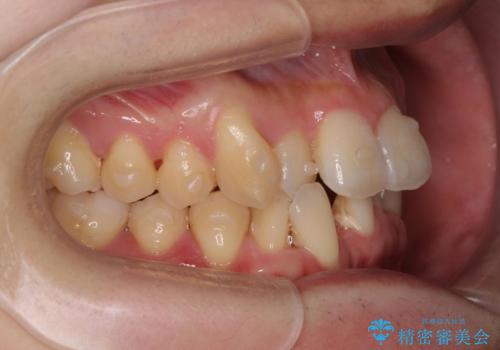

ねじれ・がたつきのある前歯を改善

- がたつき・すれ違い、ねじれのある前歯の見た目、噛み合わせの改善を希望され来院されました。

4本の小臼歯抜歯を避け、下顎前歯の1本抜歯の極力少ない抜歯本数で審美的な歯並びを得る治療計画としました。